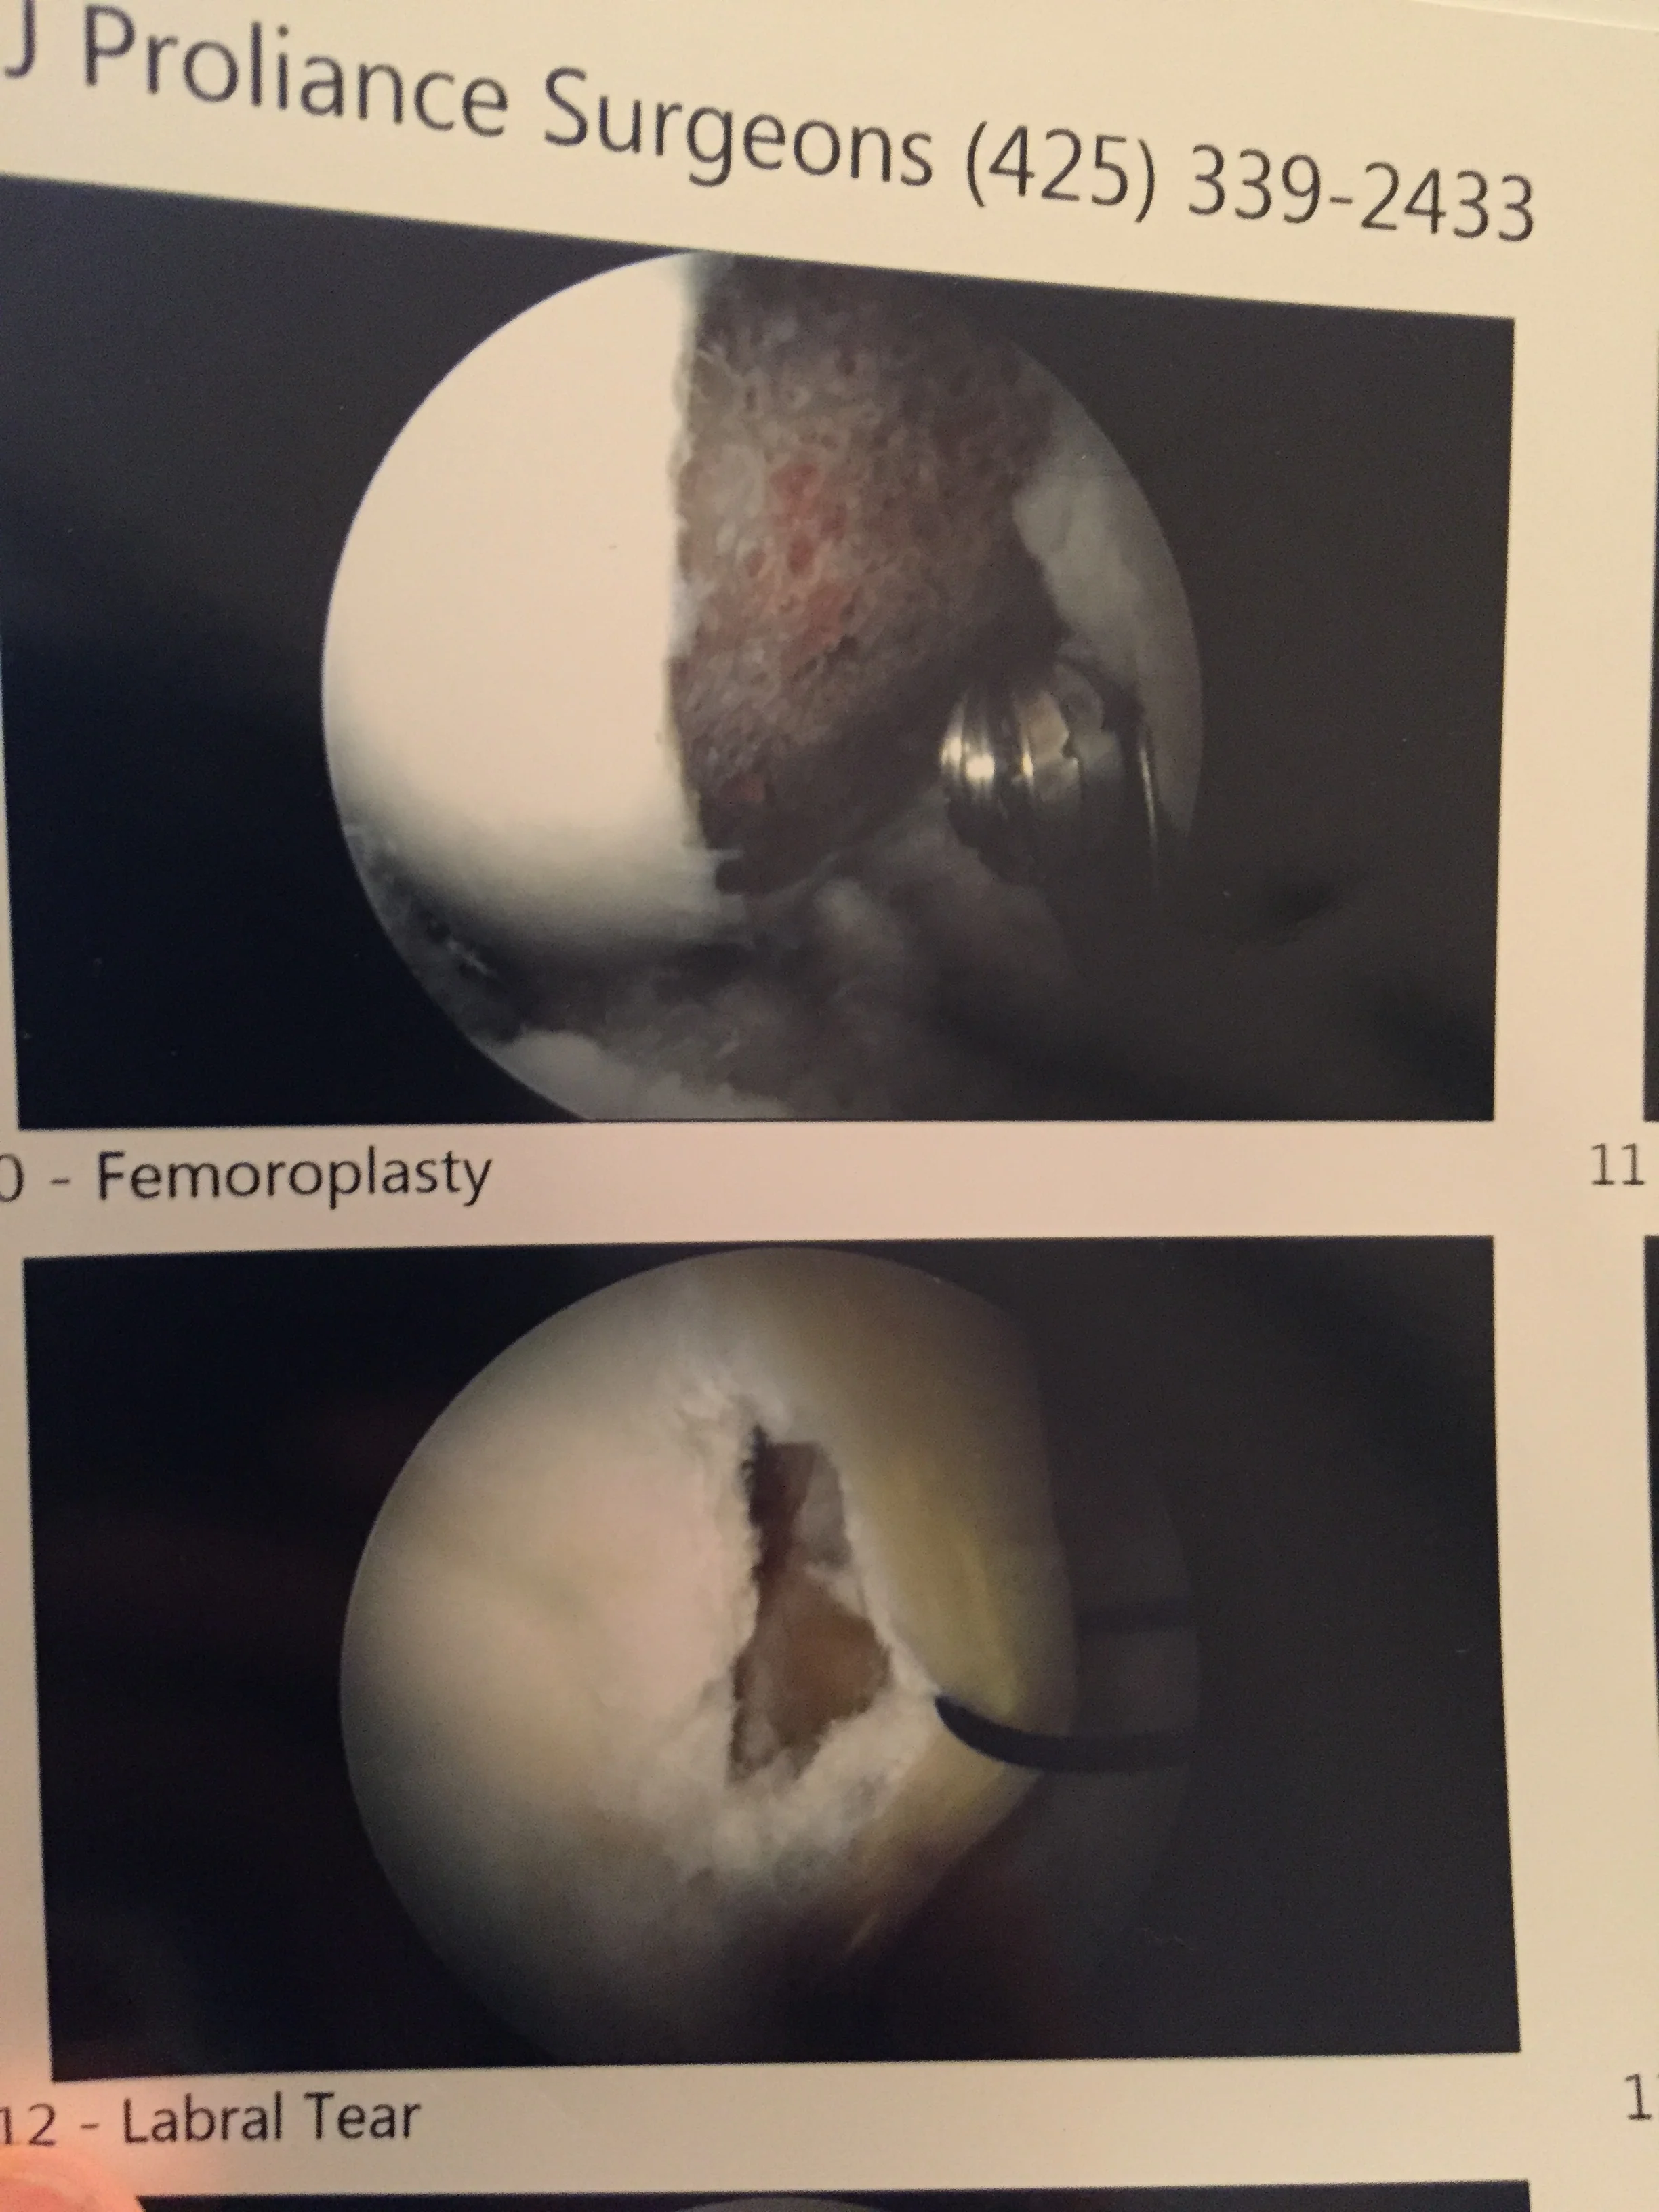

Top picture is the shaving of my femur - bottom is what it says, my tear! Pretty good, huh?

February 9th I was knocked out by anesthesia, and had a long surgery, I think 2.5-3 hours.  While I was under, my surgeon (Dr. Nowak at Everett Bone and Joint) went in, shaved my femur down (because I had too much bone on my femur, called a cam impingement) and repaired my labrum (cartilage that stabilizes the hip, and protects your articular cartilage).  He put in 2 anchors and then stitched the labrum back together.  FAI can be genetic, can occur during growth depending on the sports you play growing up, or can occur from injury.  FAI is also known as hip impingement, because of what happens during hip flexion (the acetabulum and femur impinge on each other, typically at angles of 90 or greater), and FAI consequently tears your labrum.  Not everyone who has FAI will tear their labrum (lucky them), just like not everyone who has a torn labrum has FAI, it can tear from a traumatic event.